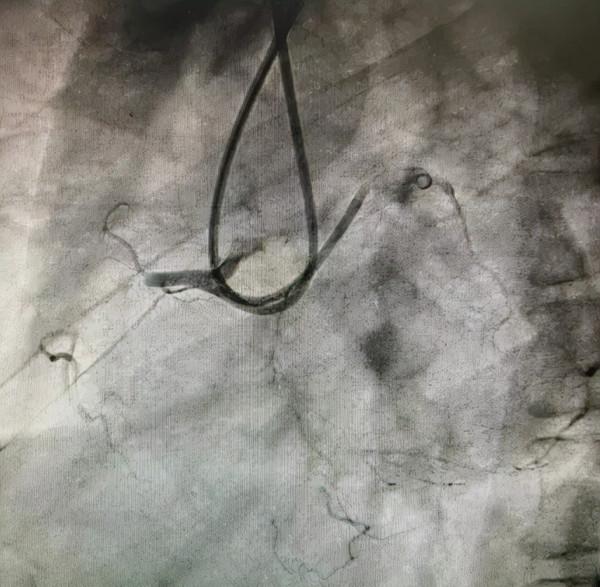

CAG分析及策略制定:冠狀動脈造影提示右冠近段閉塞:

患者右冠近段齊頭閉塞、閉塞段長、伴鈣化,側枝迴圈血管條件差,考慮逆向成功率較低。

PCI過程:術中首先嚐試正向開通(AWE),逐步升級導絲,均多次進入內膜下,反覆嘗試不能送入遠端真腔,王健主任果斷啟動正向ADR技術,利用Corsair微導管於右冠近段製造正向夾層,使用專用器械Stingray球囊,Gaia Third導絲穿刺,

成功透過血管內膜下重新進入遠端血管真腔,經過多體位投照、逆向造影均證實為真腔,順利開通閉塞病變。